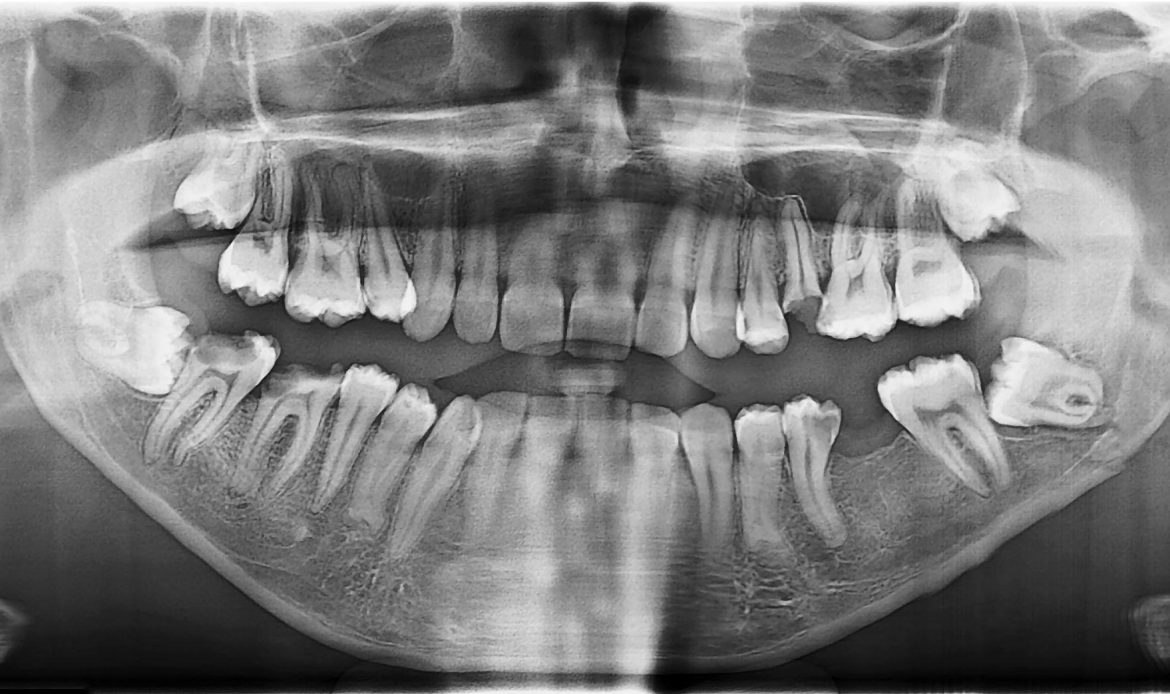

Gömülü 20’lik Diş Çekimi Daha mı Ağrılıdır?

Evet. Gömülü dişlerde:

- Kemik dokusu kaldırılabilir

- Dikiş atılabilir

- İşlem süresi uzayabilir

Bu nedenle iyileşme süresi basit çekimlere göre biraz daha uzun olabilir. Ancak doğru cerrahi teknik ve uygun bakım ile süreç kontrollü ilerler.